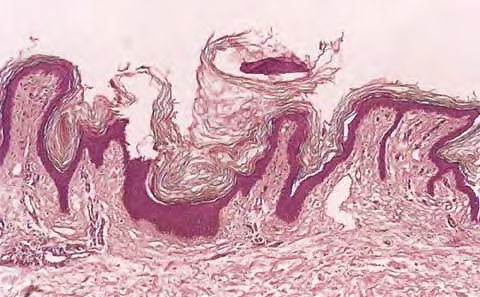

Clinically, acanthosis nigricans presents as papillomatous brown patches, predominantly in the intertriginous areas such as the axillae, the neck, and the genital and submammary regions (. In extensive cases of acanthosis nigricans of the malignant type, mucosal surfaces, such as the mouth, the vulva, and the palpebral conjunctivae, may be involved (29B). In the acral type, there is velvety hyperpigmentation of the dorsa of the hands and feet.

Histologic examination reveals hyperkeratosis and papillomatosis but only slight, irregular acanthosis and usually no hyperpigmentation. Thus, the term acanthosis nigricans has little histologic justification.

In a typical lesion, the dermal papillae project upward as finger-like projections. The valleys between the papillae show mild to moderate acanthosis and are filled with keratotic material . Hom pseudocysts can occur in some cases . The epidermis at the tips of the papillae and often also on the sides of the protruding papillae appears thinned.